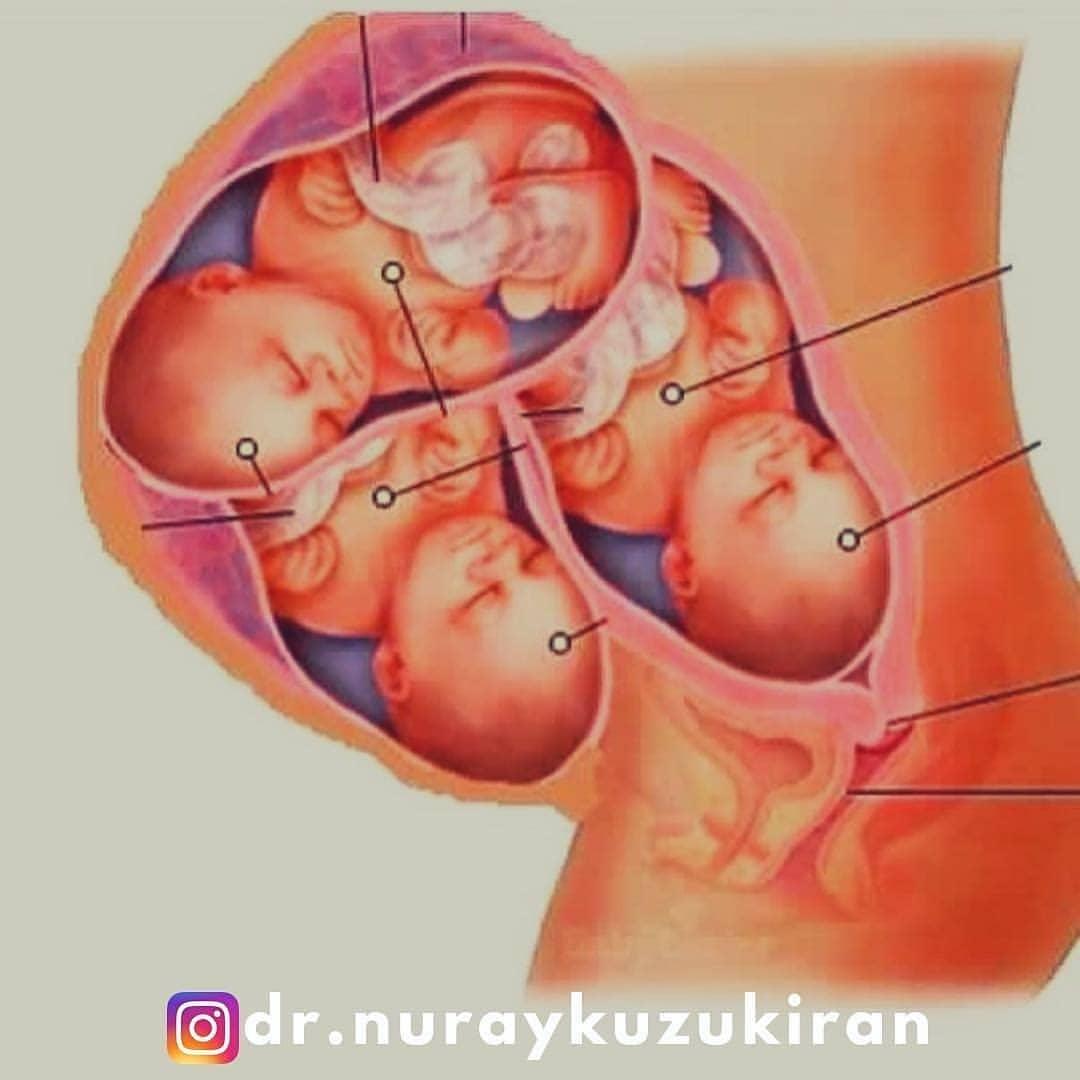

25 недель беременности: Как выглядит будущий малыш

Раздел: Образы вокруг